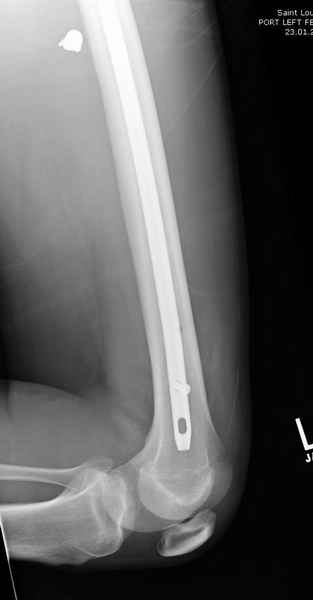

Учитывая, что больной получил травму не во время визита в церковь, и он является одним из представителем 40 миллионного “outstanding itizen”, без медицинской страховки, без работы в свои 39 лет, и без надлежающей ортопедической дисциплины у которого отсутсвует страх стрессового перелома, было рекомендовано оперативное лечение: профилактическое антеградное интрамедуллярное штифтование.

Методика штифтования при отсутствии большой зоны перелома как при онкологических профилактических штифтованиях, расверливание интрамедуллярного канала проводим с предварительным наложением дополнительного дренажного отверстия в дистальном отделе бедра (в данном случаи в канале оставили 6.5 мм канюлированный шуруп), иначе при создании давления в канале во время сверления имеется опасность эмболизации легочной артерии тромбом.